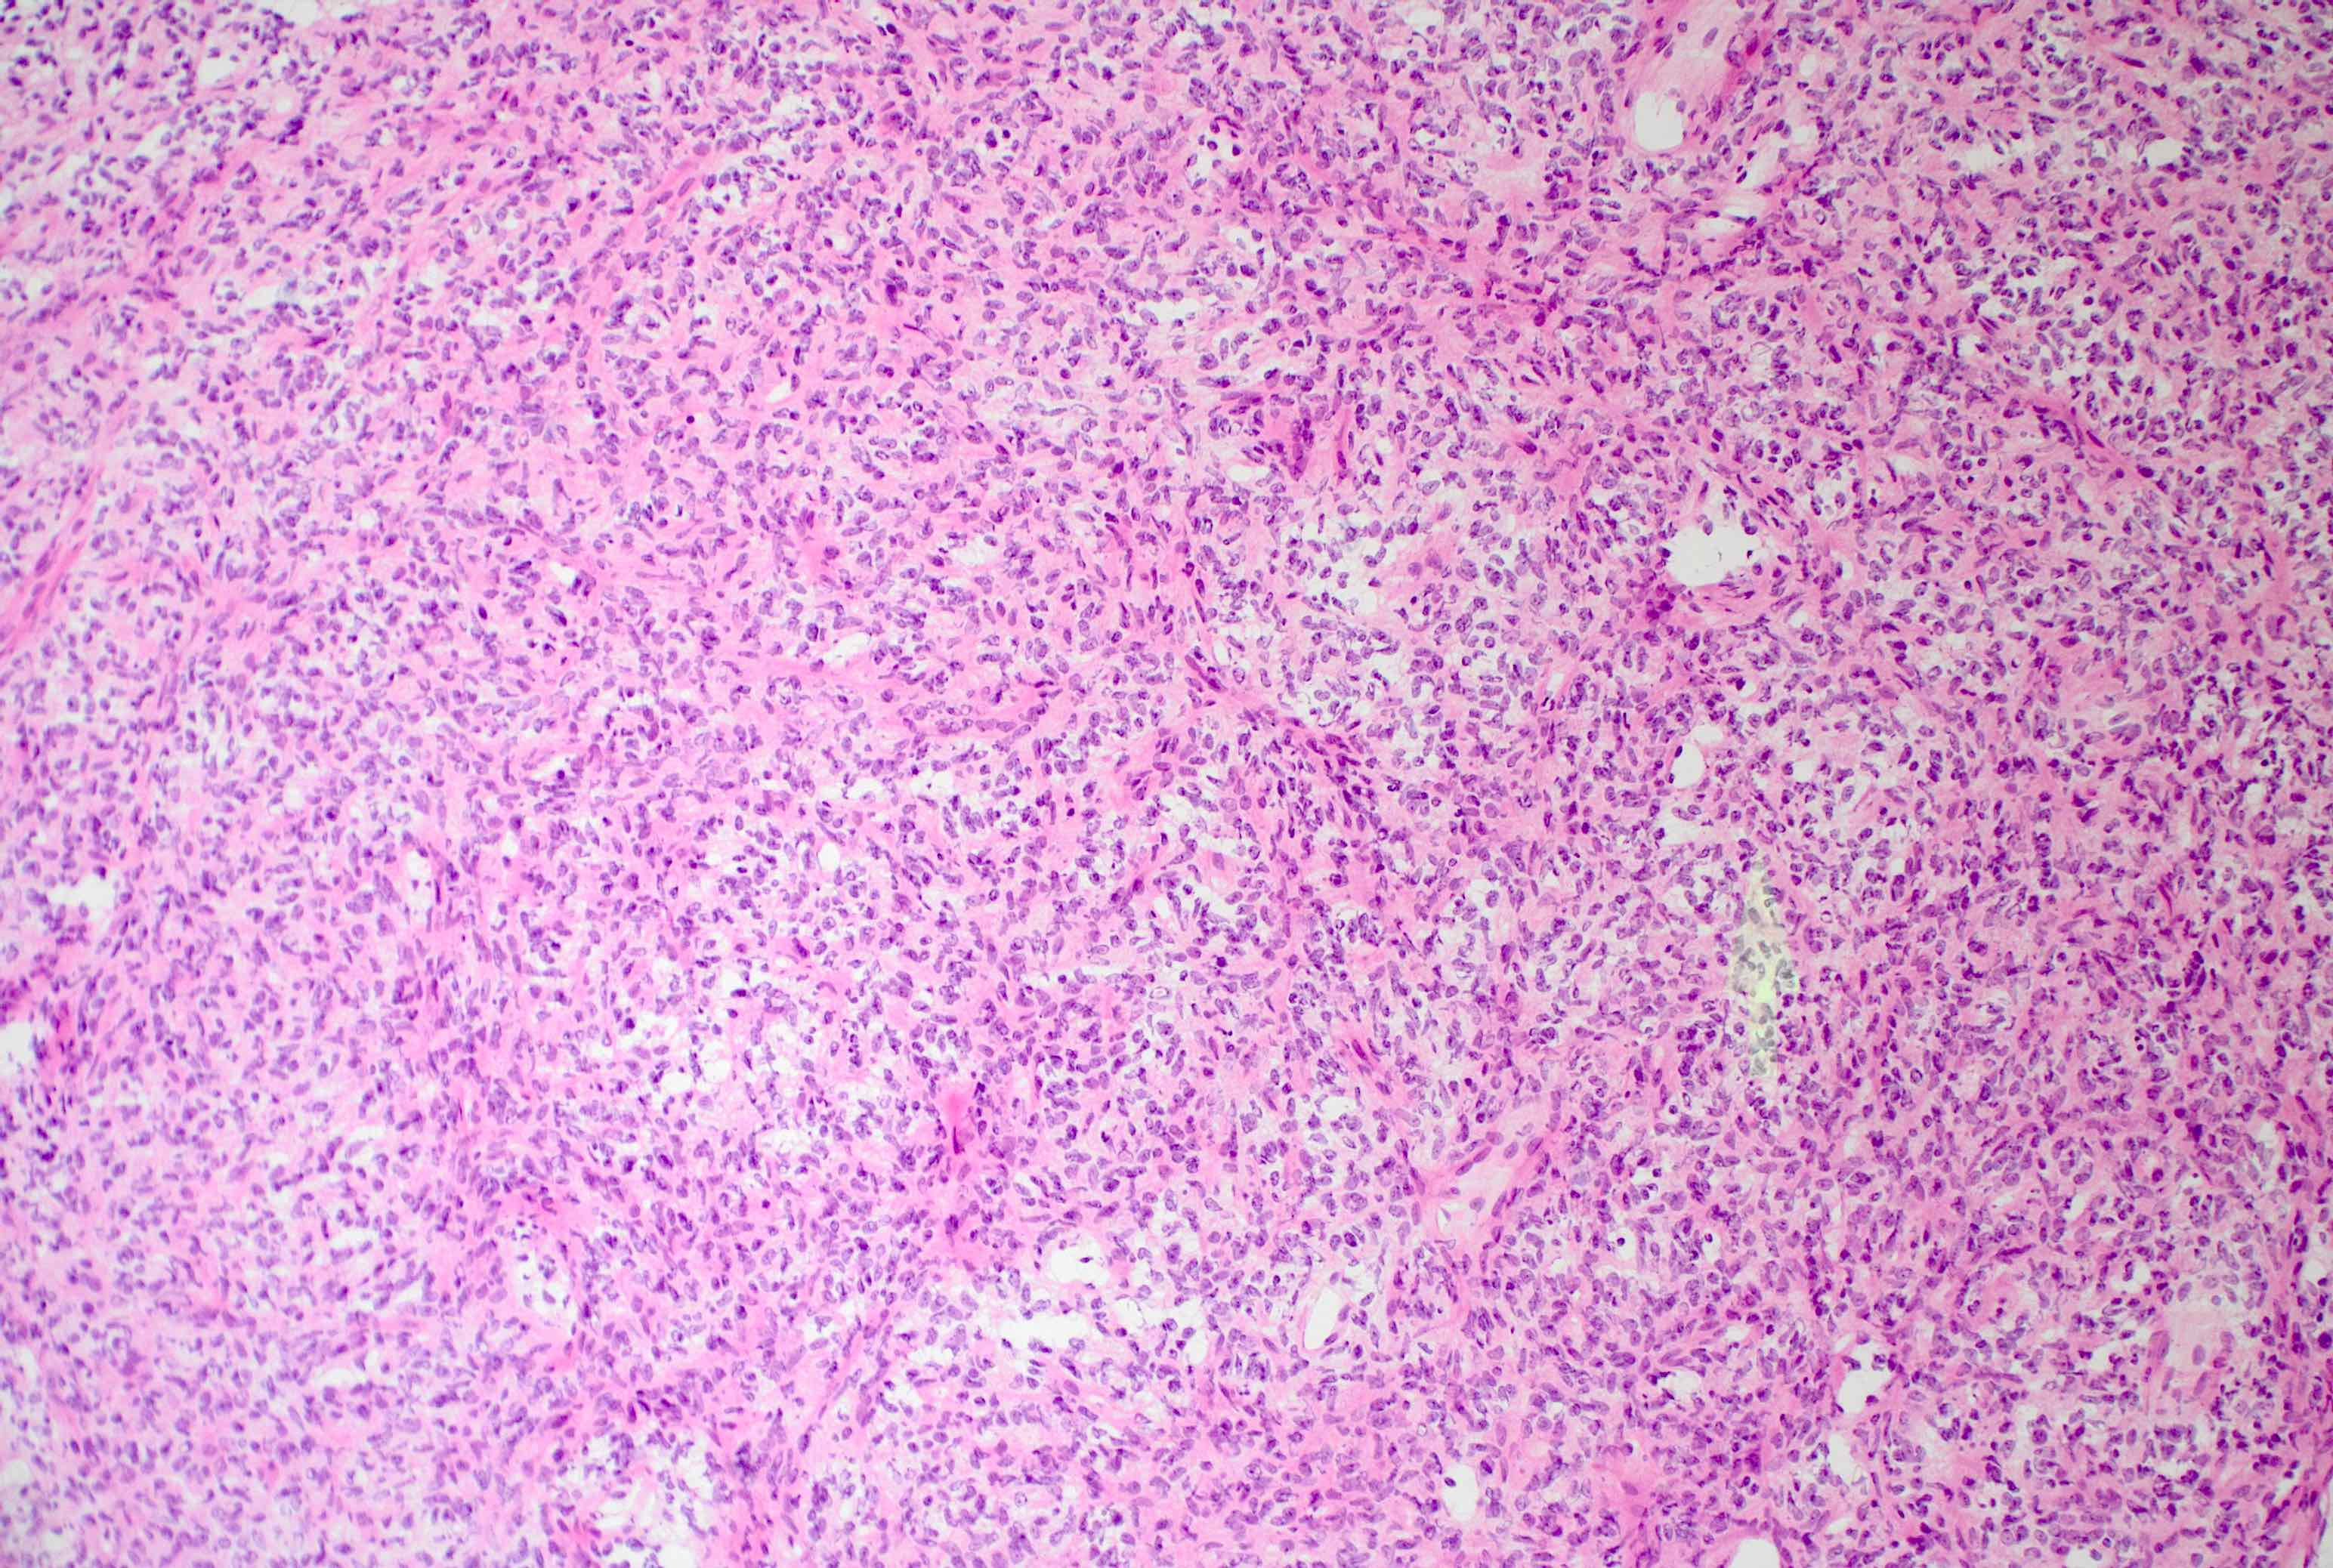

Microscopic (histologic) description

- Essential: patternless pattern of spindle cells, often solid but can also have papillary and other architectures, arranged around branching hyalinized vessels

- Varying amounts of stromal collagen and overall cellularity

- Nuclei are bland, without features seen in mimicking neoplasms

- WHO grading criteria:

- < 5 mitoses/10 high power fields (HPF) = grade 1

- ≥ 5 mitoses/10 HPF = grade 2

- ≥ 5 mitoses/10 HPF with necrosis = grade 3

- Often has staghorn vasculature

Microscopic (histologic) images